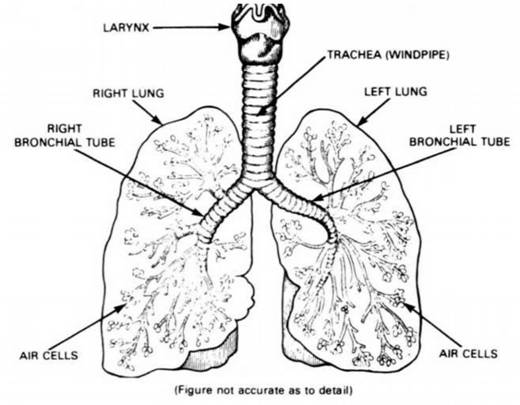

YOUR LIFE IS IN YOUR BLOOD. Overweight - Too Fat is Dangerous! Your LUNGS. Your Life and Your Health at Stake: Avoid Tobacco